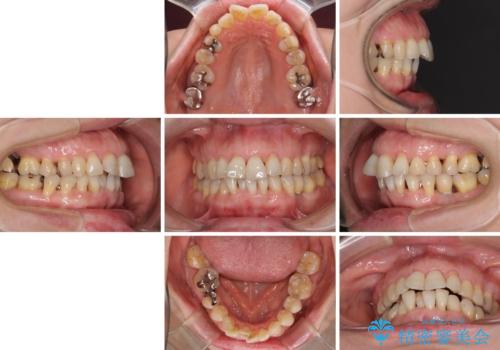

口元の出っ張りとデコボコを改善したい

- 近医にてインプラント治療を行った後に矯正治療を希望され、来院された患者様です。

口元の突出感とデコボコが気になっているとのことでしたが、インプラントが既に3本埋入されていたため、抜歯矯正による口元を引っ込めることができない状況でした。

近医での歯周病治療の影響でブラックトライアングルが発現していたため、IPR(歯と歯の間を削る)で隙間を改善しつつ、インプラントを固定源に歯列全体を後方へ移動させることとしました。